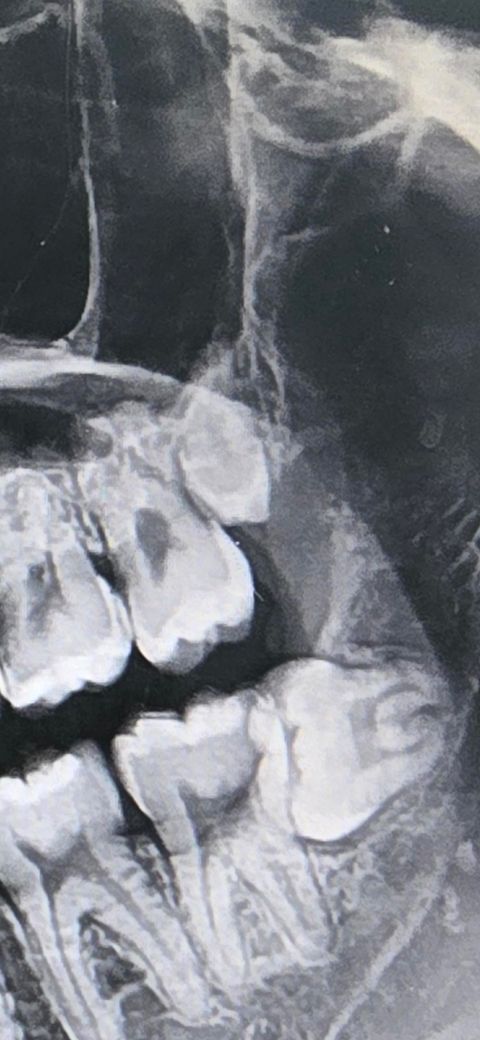

위쪽 사랑니 어떻게 생긴 사랑니인지 알수있나요?

위에 있는 사랑니가 일반적인 사랑니랑 다르게 생겼는데 자라다 만 사랑니인가요? 아님 방향이 돌아가있는건가요?

씹는면이 약간 정면 보고 있는거같기도 하고?

위의 사랑니가 잇몸에 묻혀 있는 상태 즉 매복사랑니 입니다. 사랑니 사이즈가 조금 작습니다. 위의 사랑니는 사이즈가 작은 경우가 종종 있습니다.

사랑니가 왜소치라고 생각하시면됩니다. 그냥 다른 치아에 비해서 작은거죠. 잇몸에 살짝 뭍혀 잇는 상태 같습니다.

왼쪽 위의 사랑니가 왜소치 형태로 작게 발생이 된 것으로 보입니다. 맹출되지 않았다면 크게 문제가 되지 않기 때문에 그냥 사용해도 됩니다.

위에 있는 사랑니가 일반적인 사랑니랑 다르게 생겼는데 자라다 만 사랑니인가요? 아님 방향이 돌아가있는건가요?사랑니는 원래 형태가 다양합니다.

각도는 정상인데 왜소한 사랑니입니다 원래 사랑니는 형태상 변이가 많습니다 불편하면 발치하시면 됩니다